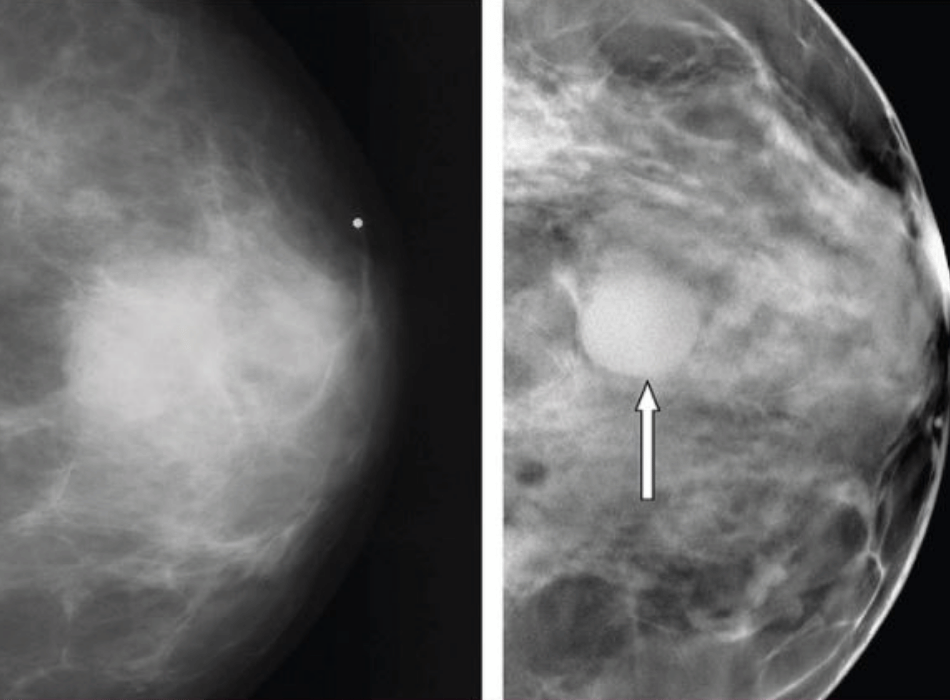

Mamografi

Düzenli taramalar, meme kanserinin yayılmaya başlamadan önce erken dönemde belirlenebilmesi açısından oldukça önemlidir. Meme kanseri taramasında mamografi altın standarttır. Mamografi düşük dozda x-ray ile meme iç yapısının görüntülenmesidir.

Mamografi tetkikinde amaç, meme kanserinin mümkün olduğunca erken evrede saptanabilmesidir.40 yaş üzerindeki tüm kadınlarda, meme ile ilgili yakınması olsun veya olmasın her yıl mamografi çekilmesi, erken teşhis açısından büyük önem taşır.

Teknolojinin gelişmesi ile birlikte memeyi üç boyutlu değerlendirebilen tomosentez mamografi kullanılmaya başlanmıştır. Meme tomosentezinde, X ışını tüpü her bir memeden farklı açılardan birçok görüntü yakalayan bir yay içinde hareket eder.

Bu dijital görüntüler daha sonra bir bilgisayar tarafından üç boyutlu görüntüler halinde yeniden sentezlenir. Bu üç boyutlu görüntü setleri, kanser hücrelerini gizleyebilecek doku örtüşmelerini en aza indirmektedir.